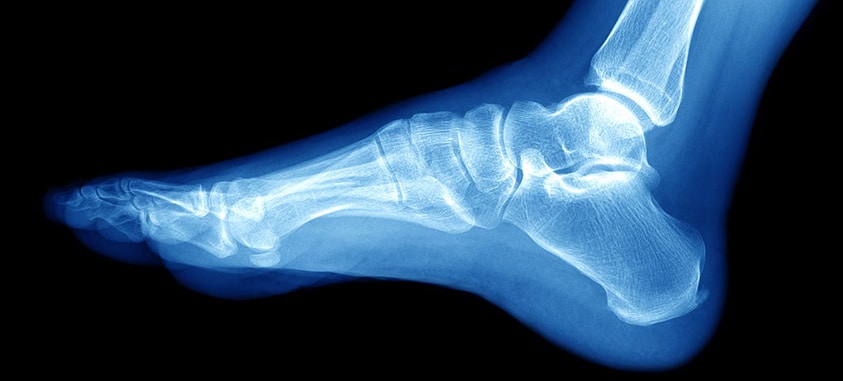

Medicul ortoped va examina piciorul și va pune întrebări despre cum s-a produs fractura, apoi va comanda o radiografie/CT/IRM. Imaginea trebuie să includă tibia și peronéul.